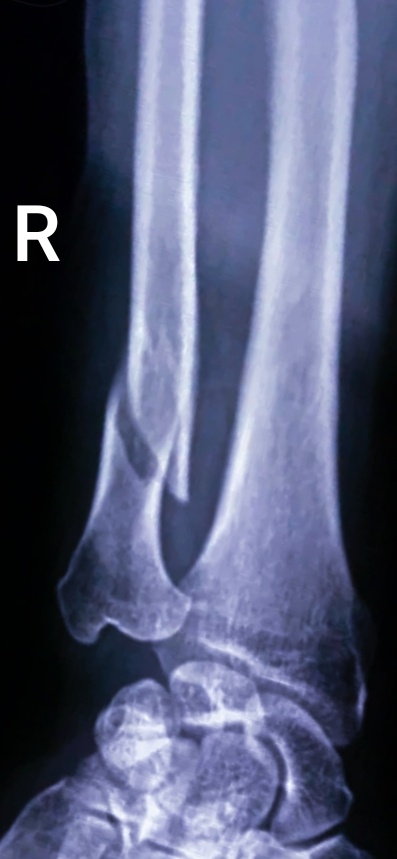

Завезли мужчину, 56 лет на сидячей каталке, сын привез.

–На стол его укладывайте,– сказала я, увидев в направление, что назначена голень.

-Что случилось с вами, уважаемый Николай? – спросила я, выйдя из пультовой с кассетой.

- Брус на ногу упал.

- Дома наверное ремонт затеяли.

-Ага, в частном доме живу, вот решил с пристройкой повозиться пока в отпуске.

–Не обрадую, - сказала я пациенту, увидев первый снимок.

-3

-Да я уже понял и без вас, там кость ходуном ходит, сходил в отпуск, называется....

–Забирайте, –пригласила я сына, – и назад к врачам.